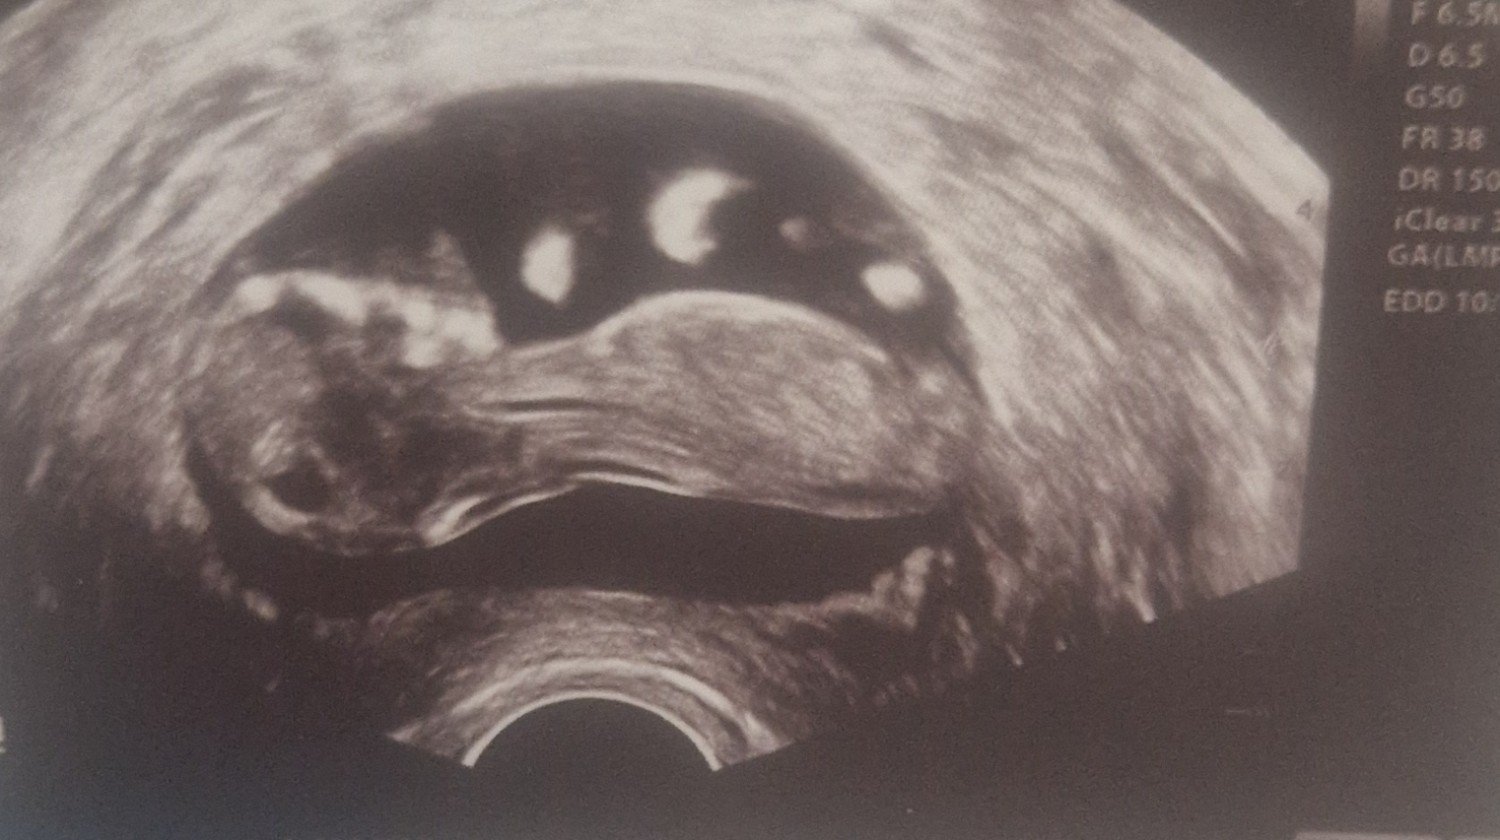

for my first unborn child. please help me raise money for my first baby. In Slovakia, it is not easy to live on a Slovak salary, especially when I am the only one working.